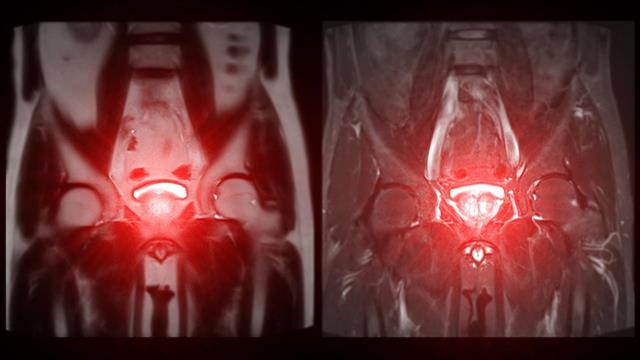

«Σε περίπτωση υποψίας καρκίνου ο ουρολόγος θα συστήσει την πιο ειδική εξέταση για την τοπική διάγνωση που είναι η πολυπαραμετρική μαγνητική τομογραφία (MRI προστάτη). Σε συνδυασμό με τη μαγνητική και ειδικά εφόσον βρεθούν σε αυτήν ύποπτες εστίες, πραγματοποιείται βιοψία προστάτη» εξηγεί ο δρ Νικόλαος Α. Κωστακόπουλος MD, PhD, FEBU Χειρουργός Ουρολόγος-Ανδρολόγος, Εξειδικευμένος στη Ρομποτική Ουρολογία, Επιμελητής A΄ Ουρολογικής Κλινικής Metropolitan General, Διδάκτωρ Πανεπιστημίου Αθηνών ΕΚΠΑ.

Υπάρχει πλέον διαθέσιμο το πιο σύγχρονο σύστημα βιοψίας προστάτη, το Fusion Biopsee, με δυνατότητα σύντηξης της εικόνας της μαγνητικής τομογραφίας και του υπερήχου, για τη λήψη βιοψιών ακόμα και από τις πιο μικρές ύποπτες εστίες, μεγέθους λίγων χιλιοστών.

«Με ειδικό λογισμικό», εξηγεί ο ειδικός, «συνδυάζονται οι εικόνες της πολυπαραμετρικής Μαγνητικής Τομογραφίας που έχει κάνει ο ασθενής, με τον υπέρηχο του προστάτη, ώστε να εντοπιστούν και να χαρτογραφηθούν σε ζωντανό χρόνο, με ακρίβεια χιλιοστού, οι ύποπτες εστίες, από τις οποίες χρειάζεται να ληφθούν βιοψίες. Μαζί με τις ύποπτες εστίες λαμβάνονται και τυχαίες αντιπροσωπευτικές βιοψίες από όλο τον προστάτη, ώστε να επιτευχθεί η σωστή διάγνωση.